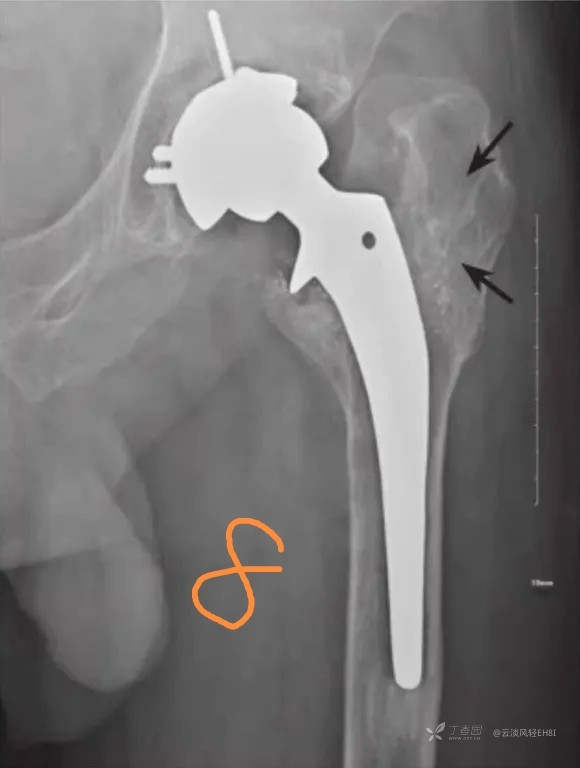

二、感染(图3)

人工髋关节置换术后感染是常见而又极其严重的并发症,感染经久不愈及扩大将导致死骨形成及假体松动。X线检查主要有以下几方面表现:①假体周围出现透亮带,透亮带轮廓不规则,宽窄不等,呈花边样,部分伴硬化边缘;②假体出现松动移位;③股骨柄髓腔内、外侧骨质破坏伴死骨及骨膜新生骨形成;④行造影时有腔道与关节相通。以上征象有时难以和无菌松动区别,结合临床上出现局部红肿热痛,可考虑深部感染的存在。